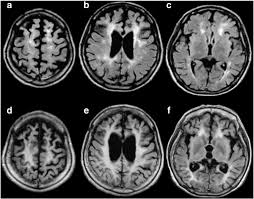

What do we know about Binswangers disease. CADASIL cerebral autosomal dominant arteriopathy with subcortical infarcts and leukoencephalopathy is a hereditary small artery disease which is phenotypically similar to Binswangers disease BD a nonhereditary form of small artery disease. They concluded that Binswangers disease is probably due to chronic or acute-on-chronic white matter ischemia.

Binswanger disease is a sporadic disorder with no currently known hereditary predispositions. Binswangers disease BD also called subcortical vascular dementia is a type of dementia caused by widespread microscopic areas of damage to the deep layers of white matter in the brain. Polycystic kidney disease is when the kidneys see cysts forming on them. Certain rare hereditary diseases such as cerebral autosomal dominant arteriopathy with subcortical infarcts and leukoencephalopathy CADASIL may also lead to Binswangers disease. Illness or sickness in general. Of course the kidneys are necessary for getting rid of toxins from the body. A genetically transmitted form of the disease is known as familial arteriopathic leukoencephalopathy or CADASIL cerebral autosomal dominant arteriopathy with. Although Binswangers disease is not considered an inherited condition genetics may play a role in many of the conditions and risk factors that are associated with the. This is one of the rarer hereditary diseases but that doesnt make it unimportant.

It is also called subcortical vascular dementia which damages the deep layers of the brains white matter. Polycystic kidney disease is when the kidneys see cysts forming on them. Binswangers disease is not a specific disease. Although Binswangers disease is not considered an inherited condition genetics may play a role in many of the conditions and risk factors that are associated with the. Subcortical arteriosclerotic encephalopathy SAE also known as Binswanger disease or small vessel dementia refers to slowly progressive exclusively white-matter multi-infarct dementia. CADASIL cerebral autosomal dominant arteriopathy with subcortical infarcts and leukoencephalopathy is a hereditary small artery disease which is phenotypically similar to Binswangers disease BD a nonhereditary form of small artery disease. Binswanger disease is not a hereditary disease.